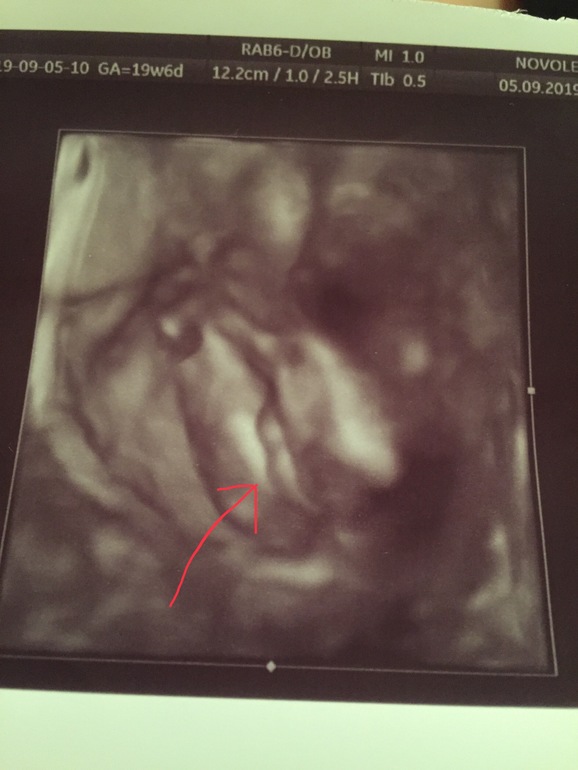

Пуповина или половой орган?

УЗИ сделано на 21 неделе, пол мужской) сегодня опять рассматривала, закрались сомнения.. как думаете?